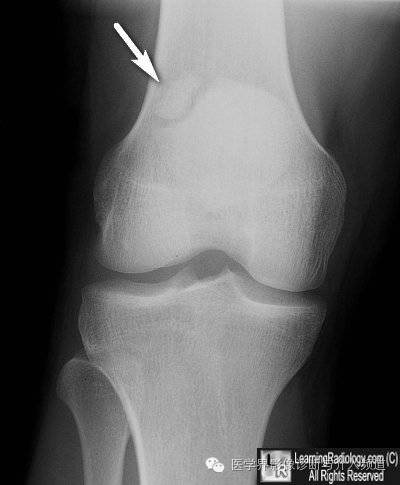

4、二分髌骨:较小的骨块通常位于外上部,通常双侧对称。